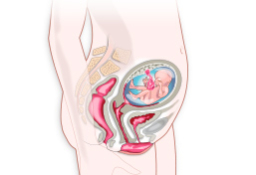

También hay que tener en cuenta que a medida que avanza el embarazo cambia el centro de gravedad y la laxitud de articulaciones y ligamentos, lo que puede predisponer a los accidentes deportivos y se toleran peor las posiciones de decúbito supino ("boca arriba") puesto que dificultan el retorno venoso produciendo mareos e hipotensión.

Cuanto mejor forma física tenga la madre, más fácil será el parto y de más salud disfrutará el bebé. Por ello, lo mejor es practicar un deporte de bajo impacto: lo más sencillo es andar a paso vivo al menos una hora al día. Casi cualquier deporte en el agua está recomendado, así como el ejercicio físico adaptado al estado de gestación.